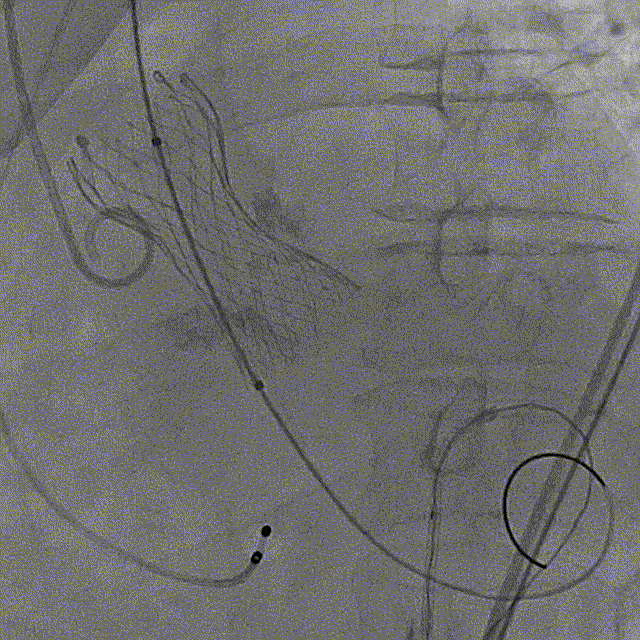

15点30,杂交手术室刚结束上台手术,患者随即进入导管室,此时患者血压为93/50mmHq、心率94次/分。病情紧急,麻醉科陈玉培教授凭借过硬功底,快速完成桡动脉穿刺测压、深静脉置管、诱导麻醉及气管插管;超声科朱叶锋先用经胸超声进行细致检查;导管室张长志护士长带领护士彭丽娟,技师杨杰同时完成了监护、导尿、仪器术前准备;介入医师进行消毒、器械准备以及瓣膜装配;ECMO小组也已经完成准备工作。

手术过程

左冠造影

右冠造影

猪尾中部初始定位

初始释放定位

瓣膜开花造影

瓣膜工作位造影

最终释放,瓣架稳定脱钩

释放后造影,可见微量反流

未见明显反流

术后即刻压差从81mmHg下降至23.9mmHg

最终造影

主动脉弓剪影,瓣膜植入深度3mm,冠脉显影正常,主动脉弓正常